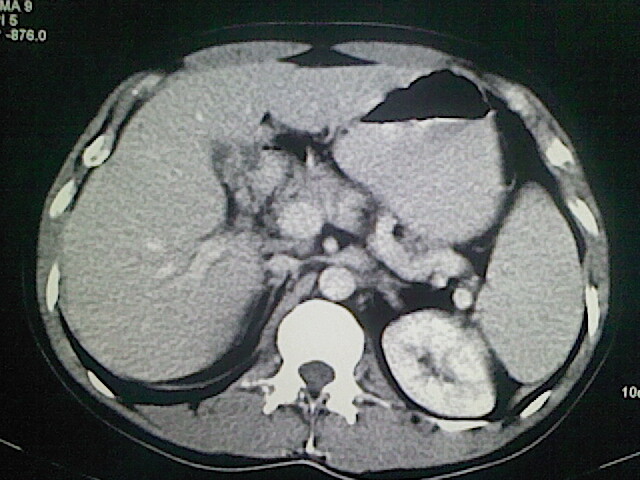

以下是引用卜一在2009-3-14 9:49:00的发言:[br]胆囊萎缩,胆囊壁不规则增厚,内部结构模糊,增强明显强化。另:肝左叶外侧段肝囊肿。支持:慢性胆囊炎!高度可疑:胆囊癌!

以下是引用余辉在2009-3-14 8:48:00的发言:[br]1)慢性胆囊炎。2)肝左叶外侧段肝囊肿。3)脂肪肝。[br]支持,胆囊萎缩,密度增高,不知b超具体有何提示,钙胆汁?结石?

以下是引用jiangjing在2009-3-14 10:18:00的发言:[br]1)慢性胆囊炎。2)肝左叶外侧段肝囊肿。3)脂肪肝。4.】建议行肝功能检查